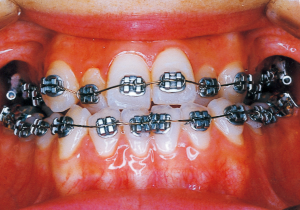

2 After Phase 2 Treatment 5-9-’92

Aware that treatment would be challenging, we proceeded with the first phase of treatment based on the current functional status and anticipated developmental implications (7). During the mixed dentition phase, the body responds readily to treatment, allowing for relatively rapid tooth movement and changes in jaw position (8,9). Subsequently, once freed from mechanical stimulation, growth continues according to inherent predispositions, often appearing to disregard occlusal functional efficiency (10,11). These changes are clearly observable on cephalometric radiographs (12). After confirming the extent and direction of growth, we decided to incorporate surgical intervention into the treatment plan and wait until the age when growth begin to decline.

13 5-21-’90 At Phase 2 Treatment

14 6-21-’90 Beginning of second phase

15 3-23-’91 Before surgery

16 5-9-’92 After Phase 2 Treatment